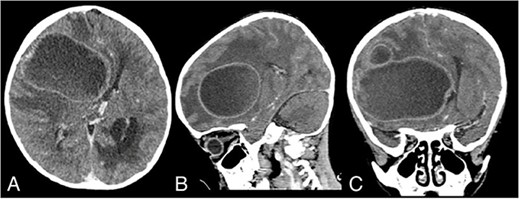

On Postoperative Day 2, the patient’s consciousness improved with GCS E2M5V2. The patient was given Ceftriaxone IV 2 × 750 mg, Metronidazole IV 3 × 110 mg, Paracetamol IV 4 × 150 mg, Captopril PO 3 × 3.125 mg, Furosemide PO 2 × 5 mg, and Digoxin 2 × 0.0625 mg. The patient was transferred to the nonintensive care ward on Postoperative Day 18. During hospitalization, the patient continued to have a fever, and he also contracted pneumonia. His sputum culture isolated Pseudomonas aeruginosa with resistance to Ampicillin, Cefepime, Ceftazidime, Meropenem, Ciprofloxacin, and Cotrimoxazole. Fortunately, the pathogen was still sensitive to Amikacin, and the patient was promptly given Amikacin IV 1 × 200 mg. The patient’s condition continued to improve, and after being 1 week free of fever, the patient was discharged after 50 days of hospitalization. His GCS on discharge was E3M5V2, with oxygen saturation of 70–80% without supplemental oxygen. A noncontrast head CT scan on discharge showed that the abscess had been completely removed (Fig. 2A–C).

Discharge noncontrast head CT scan showing that the abscess has been completely removed; (A) axial view; (B) sagittal view; (C) coronal view.